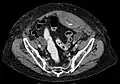

Rectus sheath hematoma seen on axial CT – with active bleeding under Marcoumar